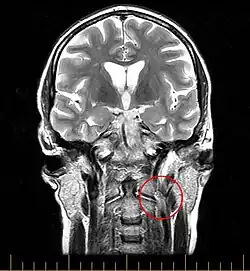

Die zuverlässigste Untersuchungsmethode um CCSVI festzustellen ist eine Katheter-Venographie. Allerdings ist diese mit einem relativ hohen Aufwand an Ressourcen verbunden und bringt für den Patienten eine nicht unerhebliche Strahlenbelastung mit sich. Deshalb wird in aller Regel davor eine Voruntersuchung mittels Magnetresonanz-Venographie sowie eine extra- und transkranielle Doppler-Sonographie[1] durchgeführt. Nur falls diese Voruntersuchungen einen hinreichenden Verdacht auf pathologische Veränderung der Venen geben, wird anschließend die Katheter-Venographie durchgeführt.